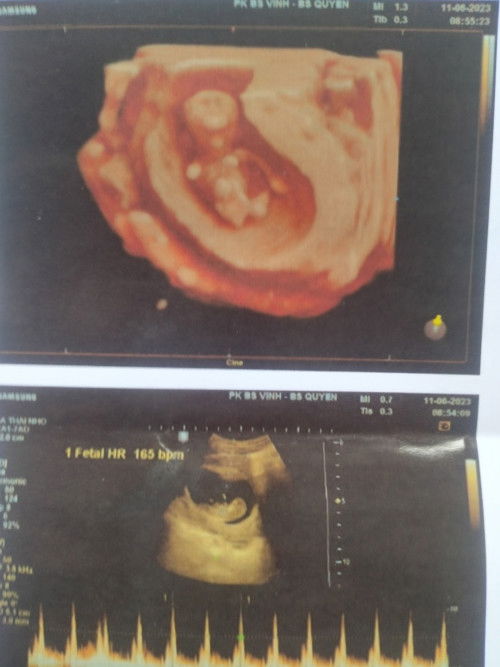

Con em được 11w tuần mà thai bị nằm thấp có bị sao không ạ